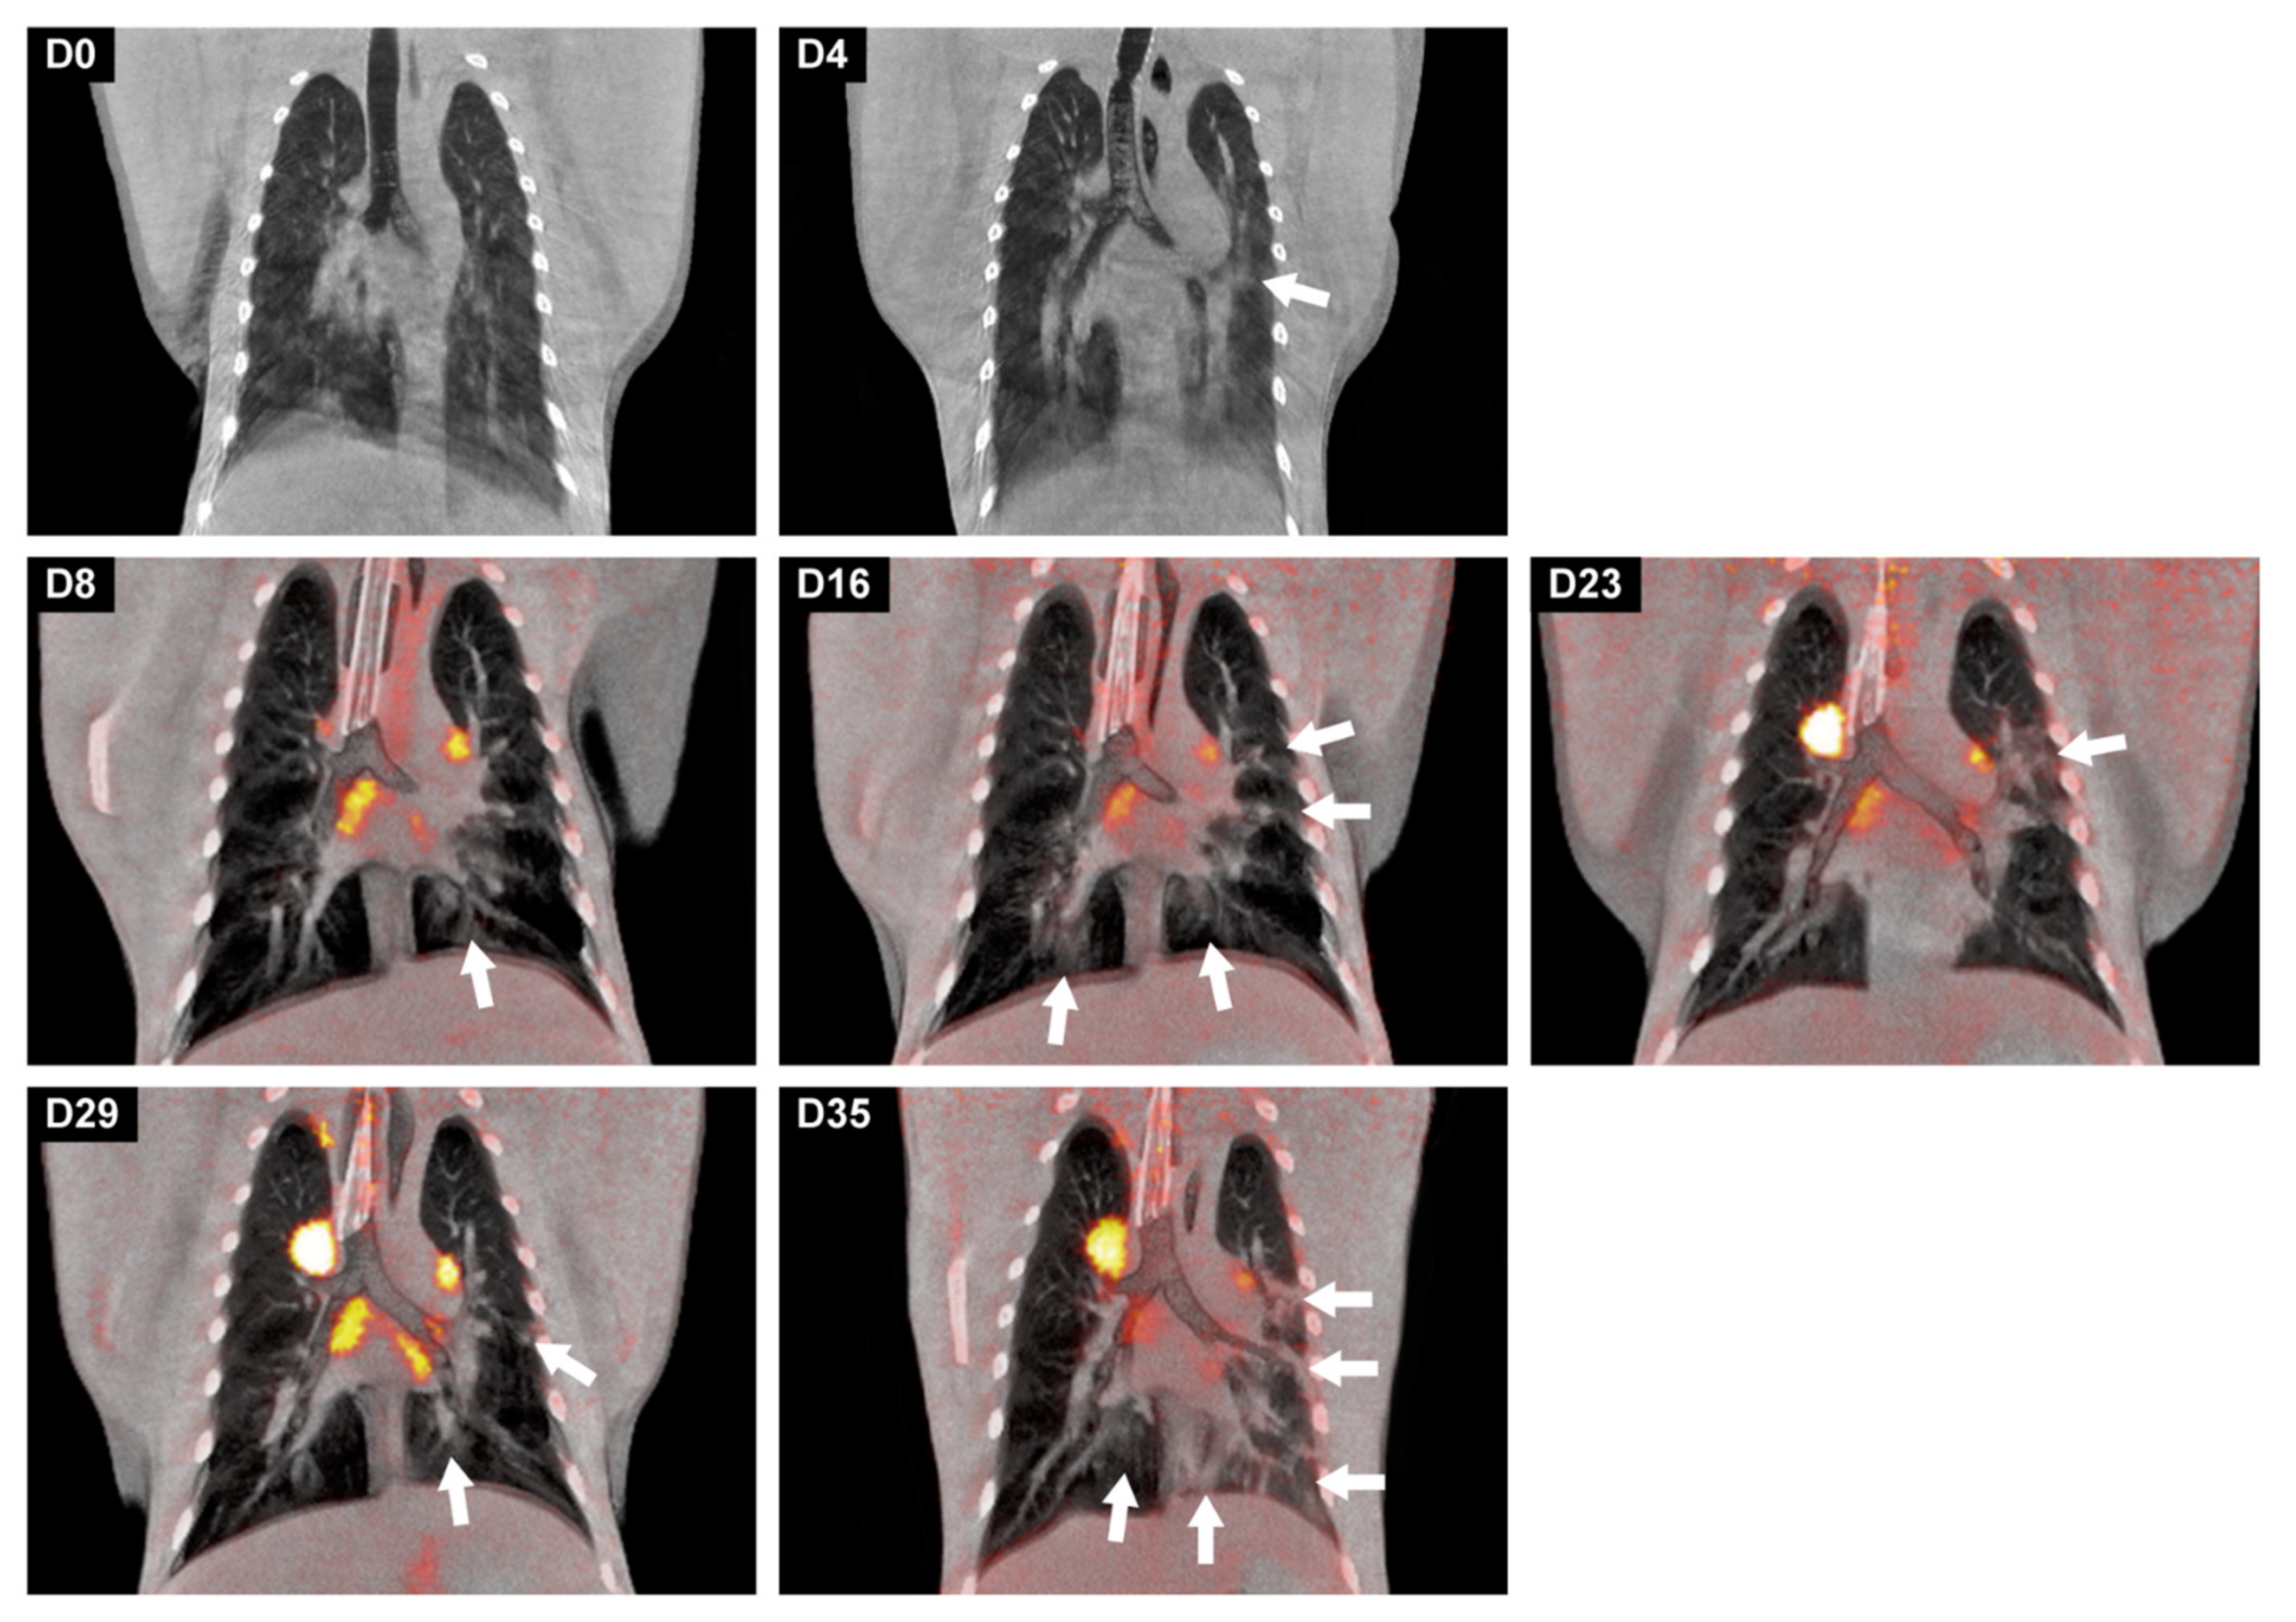

3.5. Development of Lung Lesions and Lymph Node Activation during SARS-CoV2 Infection

- Finch, C.L.; Crozier, I.; Lee, J.H.; Byrum, R.; Cooper, T.K.; Liang, J.; Sharer, K.; Solomon, J.; Sayre, P.J.; Kocher, G.; et al. Characteristic and quantifiable COVID-19-like abnormalities in CT- and PET/CT-imaged lungs of SARS-CoV-2-infected crab-eating macaques (Macaca fascicularis). bioRxiv 2020. [Google Scholar] [CrossRef]

- Pan, F.; Ye, T.; Sun, P.; Gui, S.; Liang, B.; Li, L.; Zheng, D.; Wang, J.; Hesketh, R.L.; Yang, L.; et al. Time Course of Lung Changes at Chest CT during Recovery from Coronavirus Disease 2019 (COVID-19). Radiology 2020, 295, 715–721. [Google Scholar] [CrossRef] [Green Version]

- Hartman, A.L.; Nambulli, S.; McMillen, C.M.; White, A.G.; Tilston-Lunel, N.L.; Albe, J.R.; Cottle, E.; Dunn, M.D.; Frye, L.J.; Gilliland, T.H.; et al. SARS-CoV-2 infection of African green monkeys results in mild respiratory disease discernible by PET/CT imaging and shedding of infectious virus from both respiratory and gastrointestinal tracts. PLoS Pathog 2020, 16, e1008903. [Google Scholar] [CrossRef]